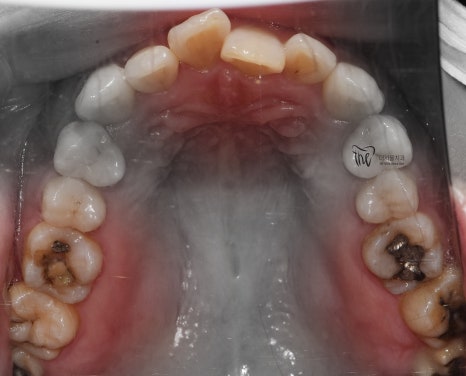

교합면에서 봤을 땐, 교정치료를 떠나서

선행해야 될 치료들이 많다는 것을 알 수 있습니다.

아말감이 수복 되어있던 곳의, 아말감 탈락에

따른 치질이 드러나 있다던지, 교합면의

다발성 우식증에 따라서 충치치료도 같이

병행을 해야 되는 상황입니다.

다만 하나 아쉬운 점은,

사랑니의 맹출 위치 불량에 따라서

바로 앞에 있는 제2 대구치는 발치 결정을

내리게 되었습니다.

이미, 치축이 상당히 쓰러져 있는 상황이며

업라이팅을 해드리기에는 시간이 오래 걸릴뿐더러

예후 또한 좋지 않을것으로 판단이 되어서

부정교합 2급 치료가 다 끝나는 시점에 맞춰서,

임플란트로 대체를 해드리기로 했죠.